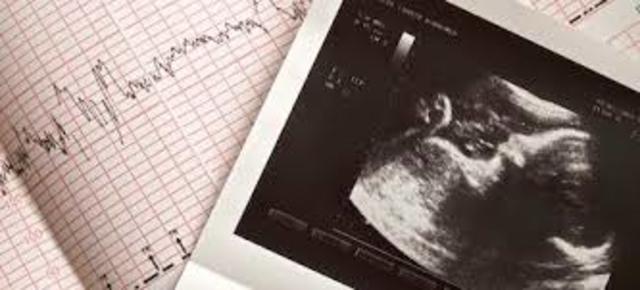

Formación de los surcos ópticos presencia de los dos primeros arcos faríngeos, inicio del latido cardiaco e incurvamiento del embrión.